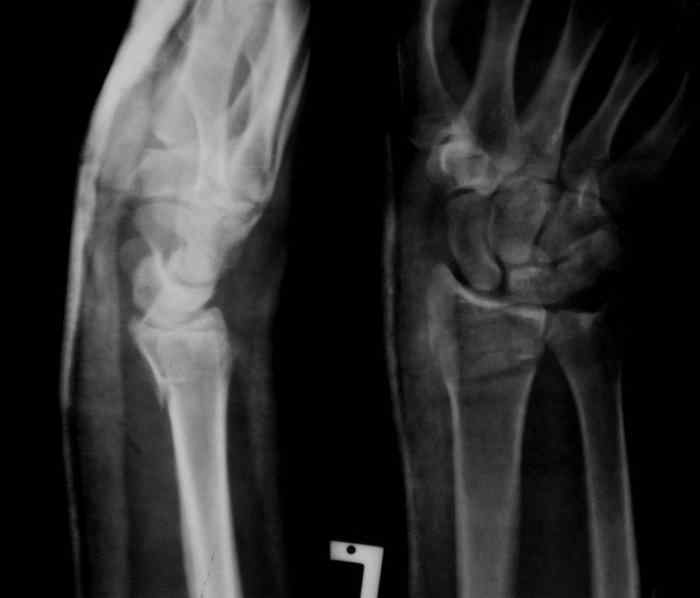

Sergey Melashenko 14 Декабрь 2007, 02:04

Под проводниковой анестезией произвел аккуратную одномоментную репозицию, фиксацию гипсовой повязкой в положении умеренной экстензии. Думаю неплохо получилось. Мягкие ткани не вызывали опасений в плане Зудека.

Спасибо.

13.12.2007.jpg

Sergey Melashenko 20 Декабрь 2007, 03:03

Сегодня контроль - все в порядке. Никакой неврологии нет.

Иногда многие вопросы можно решить грамотной репозицией. И не оперировать так часто, как сейчас.

Не сильно ли мы увлекаемся остеосинтезами... ? Как говорили корифеи, лучашая операция та , которую не сделали.